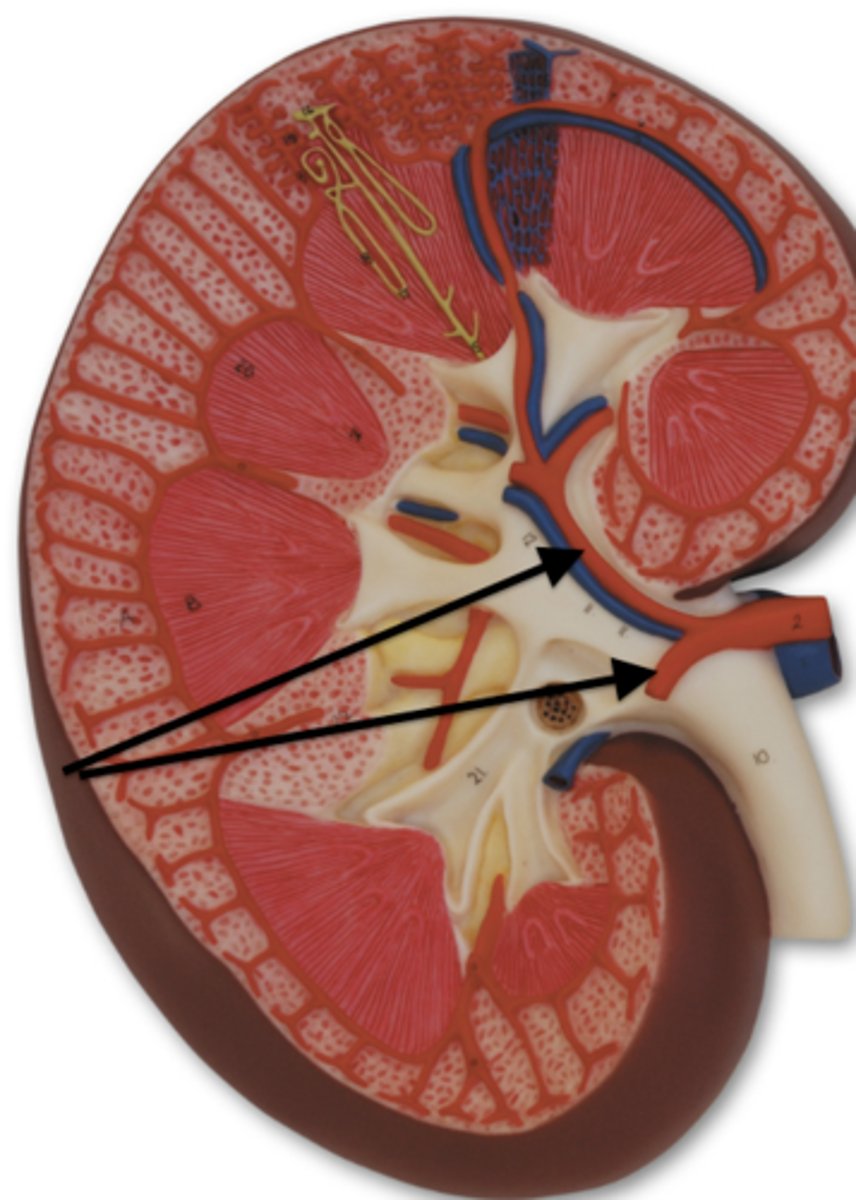

kidney

fibrous capsule

outer covering

renal cortex

renal medulla

renal papilla

major calyx

minor calyx

renal pelvis

renal pyramids

ureter

Pin in the middle

renal columns

renal artery

renal vein

segmental

both vessels

interlobar

both vessels

interlobular

both vessels

arcuate

both vessels

afferent arteriole

efferent arteriole